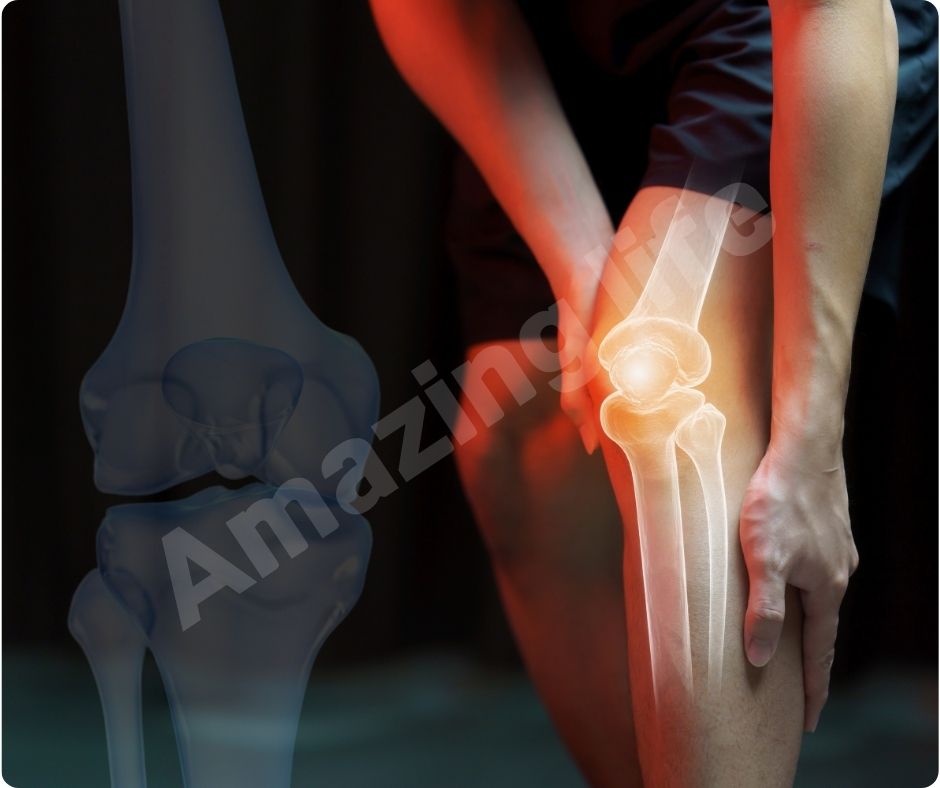

관절 통증 완화

많은 연구에서 글루코사민의 효능이 관절 통증을 완화하는 데 효과적이라는 결과가 나왔습니다. 최근 연구에 따르면, 글루코사민과 콘드로이틴 보충제를 꾸준히 섭취하면 심혈관 질환 사망률이 65%까지 감소할 수 있습니다.

연골 보호 및 재생

글루코사민은 연골 조직의 구성 요소로서 연골의 손상을 막고 재생을 촉진합니다. 이는 특히 고령자나 관절에 많은 부담이 가는 운동을 하는 사람들에게 중요합니다. 글루코사민의 연골 보호 효과는 관절염의 진행을 늦추고 삶의 질을 향상시키는 데 큰 도움을 줍니다.

염증 감소

글루코사민의 효능은 염증을 감소시키는 데도 효과적입니다. 관절염은 염증으로 인해 발생하는 경우가 많으므로, 글루코사민을 통해 염증을 줄이면 관절염 증상을 완화할 수 있습니다. 이는 자연적인 방법으로 관절 건강을 유지하는 데 유용합니다.